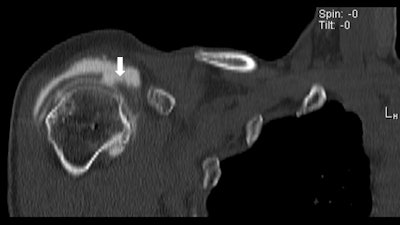

The CT image above shows a loose metallic screw (bottom arrow) and a rotator cuff tear (left arrow). The same CT below shows a second tear and loose screw (arrow). All images courtesy of Dr. Thomas Magee.

By comparison, the MR arthrogram offers virtually no details of the loose screw or rotator cuff tear.Significant findings